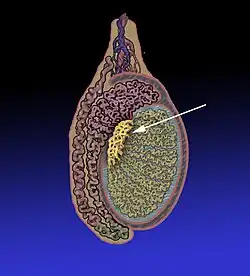

Rete testis

Le rete testis est un réseau de canaux des testicules issus des tubes séminifères droits dans le mediastinum testis.

Les canaux du rete testis s'écoulent dans les canaux efférents, qui passent dans la tête de l'épididyme. À ce niveau, le rete testis ne contient que des cellules de Sertoli, puisque tous les spermatozoïdes se trouvent dans la lumière des tubes séminifères.